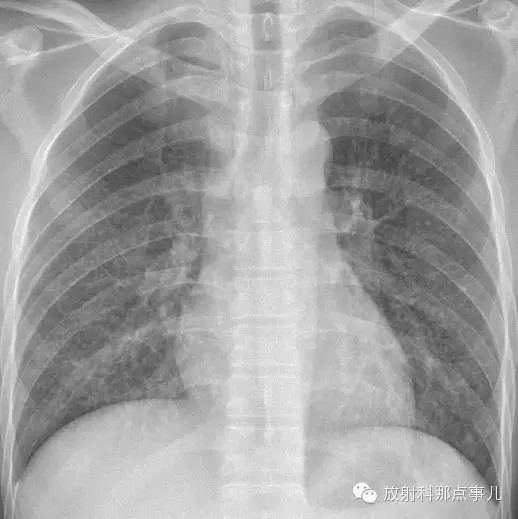

影像表现

1.胸片示双肺网状纹理,弥漫分布粟粒样病灶,由上至下病灶逐渐增多。

2.CT示双肺网状纹理,弥漫分布粟粒样病灶;HRCT示左肺上叶舌段肺气囊。